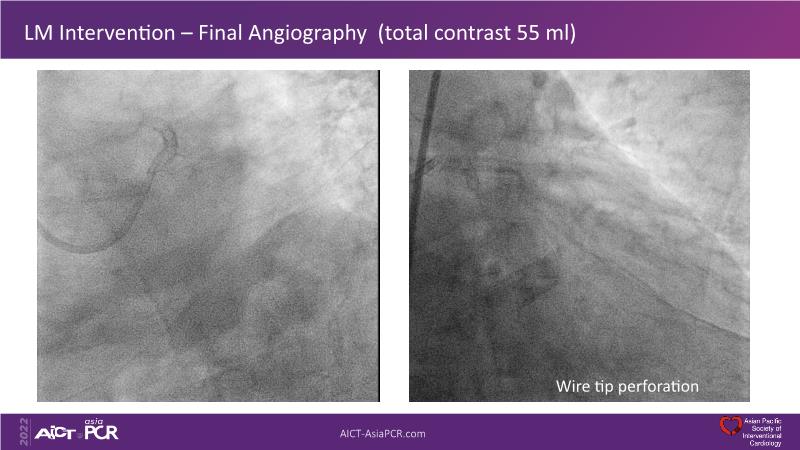

In this session, presenters describe how to use IVUS and physiology in the assessment of left anterior descending and/or left circumflex ostium in distal left main disease. Discover in the second part the general principles and clinically validated strategies for ultralow contrast coronary angiography and zero contrast percutaneous coronary intervention.

- To learn how imaging can help with strategising left main PCI, plaque preparation, device sizing and optimising results

- To learn the techniques to reduce contrast in treating complex multivessel disease with state-of-the-art tools (wiring, angiogram, etc.)